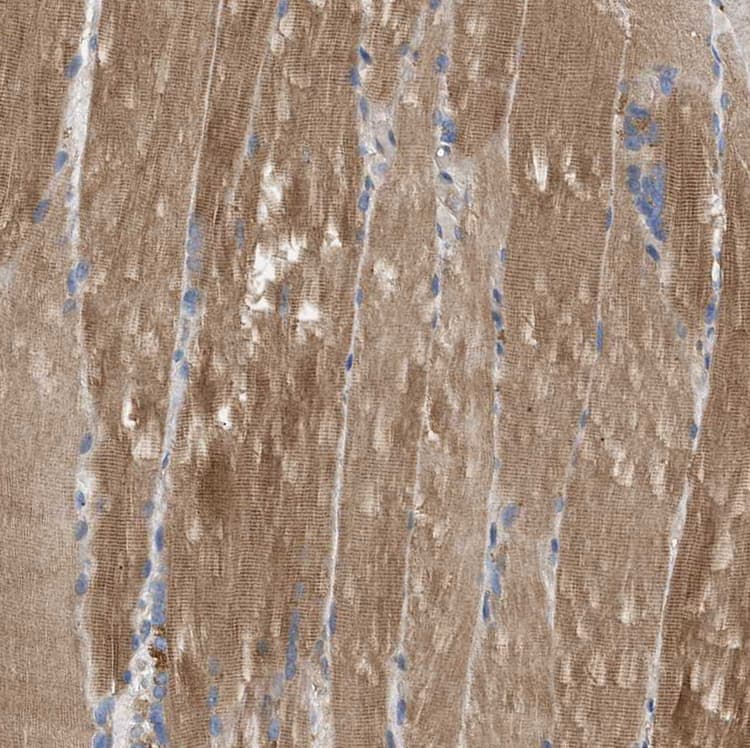

Rabbit Polyclonal PPM1B antibody. Suitable for IHC-P, WB, ICC/IF and reacts with Human samples. Cited in 1 publication. Immunogen corresponding to Recombinant Fragment Protein within Human Protein phosphatase 1B aa 350 to C-terminus.

Applications ICC/IF, IHC-P, WB

Species Reactivity Human